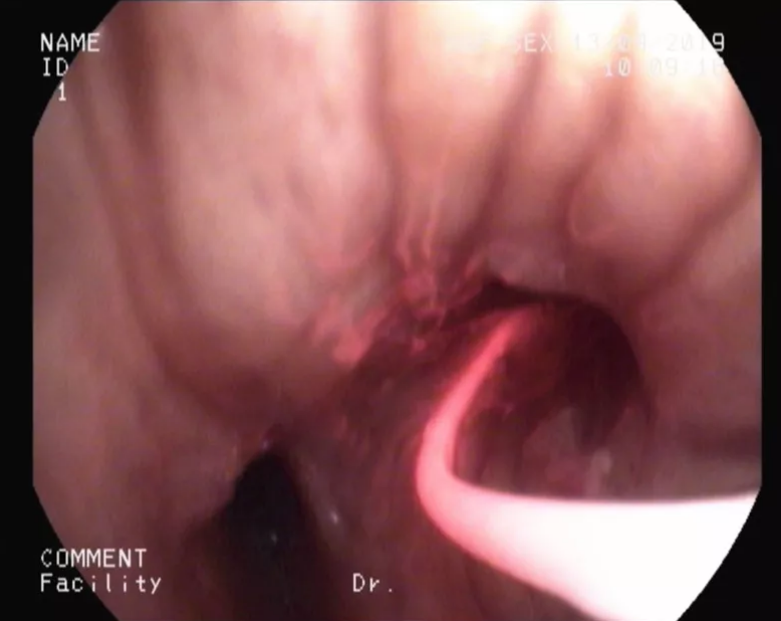

經(jīng)過(guò)光動(dòng)力治療后,患者右肺下葉基底段支氣管殘端的腫瘤明顯縮小、減少(見(jiàn)圖)。短期內(nèi)(術(shù)后3天)可見(jiàn)明顯治療效果,術(shù)后患者恢復(fù)良好,咳嗽、咯血、呼吸困難明顯緩解,且無(wú)明顯不良反應(yīng)。

治療后